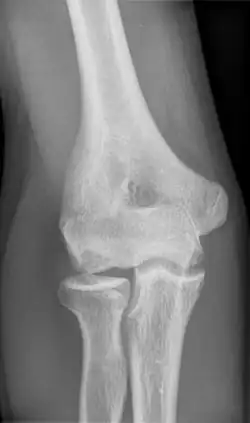

| Morbus Panner Osteonecrosis in condylus radialis humeri |

Panner disease is an osteochondrosis of the capitellum of the elbow.[1] Panner disease is primarily seen in boys between the ages of five and ten years old.[2] Panner disease is often caused by excessive throwing due to valgus stress. The disease causes pain and stiffness in the affected elbow and may limit extension; the affected elbow is usually on the dominant arm the child uses.[3] The disease may be associated with pitching and athletic activity. On radiographs, the capitellum may appear irregular with areas of radiolucency. Treatment is symptomatic, with a good prognosis. Treatment is minimal and includes restricting athletic activity to allow for the elbow to heal and for pain to be relieved.[4] The disease is named after the Danish radiologist Hans Jessen Panner (1871–1930).

To confirm the diagnosis, an x-ray or MRI scan will be done. The radiograph will enable the doctor to visualize irregularities and see the shape of the capitellum and also visualize the growth plate. In Panner Disease, the capitellum may appear flat and the bone growth plate will look irregular and fragmented. The areas where bone breakdown has occurred can also be visualized on the radiograph.[2] When the patient undergoes an MRI scan any irregularities of the capitellum will be able to be visualized, and the bone will be able to be visualized in more detail to determine the extent of swelling, if any. In the MRI results for Panner disease, there will be a decreased signal intensity of the capitellum on a T1 series and increased signal intensity on a T2 series.[2][5]